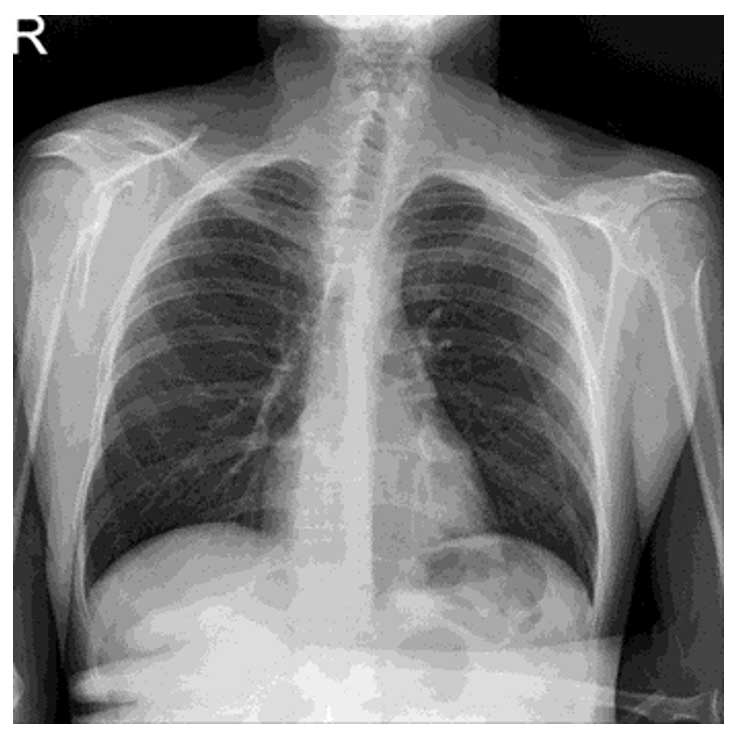

Ameliyat Sonrası: Röntgende sol total klavikulektomi ameliyatı görülmekte.